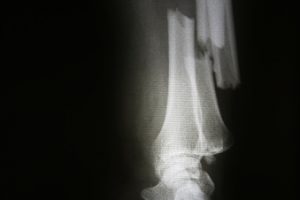

A new study has found that weight loss surgery does not mean improved bone health. Because extra weight and obesity put added strain on bones, making them weaker over time, one would think that bone health may improve with weight loss. The results of the study found that patients who underwent weight loss surgery were actually in greater jeopardy of bone fractures, compared to those who did not undergo the procedure.

After the four-year follow-up, four percent of the weight-loss patients broke at least one bone, compared to three percent in the obese group and two percent in the normal-weight group.

The reason why those who undergo weight loss surgery are at a higher risk for fractures is still unclear. Nutritional deficiencies resulting from extreme weight loss may partially explain this phenomenon.